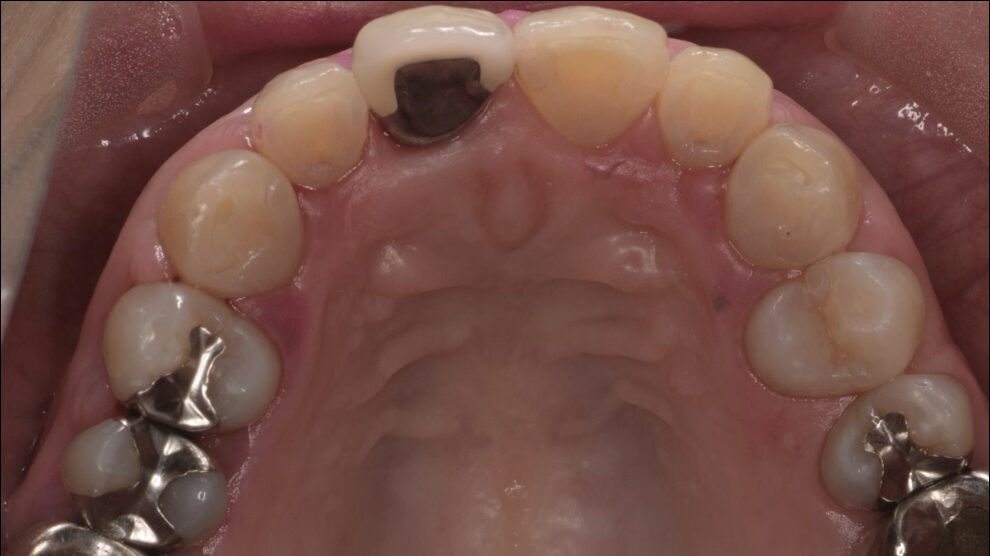

初診時